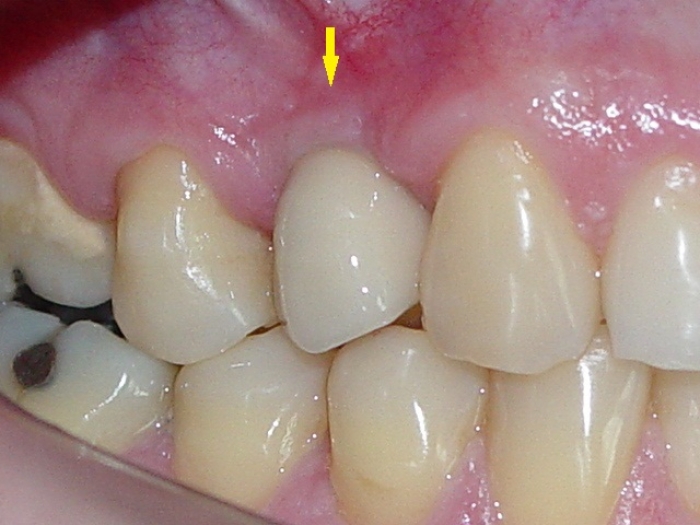

Rx e imagem da prótese fixa em porcelana sobre implante

Prótese fixa em porcelana

Imagem aproximada da prótese fixa em porcena instalada